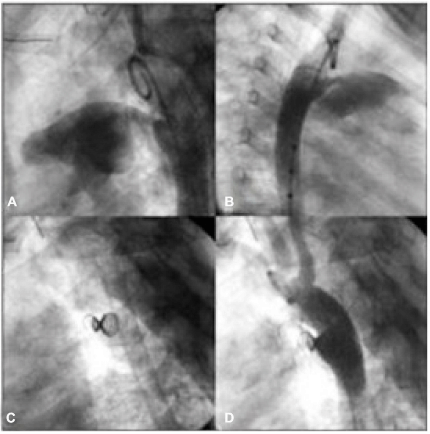

Na figura abaixo, observa-se uma oclusão de ducto arterioso. A e B: A ortografias demonstrando canal arterial tipo A, com diâmetro mínimo de 3,7 mm (milímetros) e ampola aórtica de 11 mm (milímetros); C: Dispositivo liberado com morfologia em duplo cone; D: Aortografia final com mínimo fluxo residual.